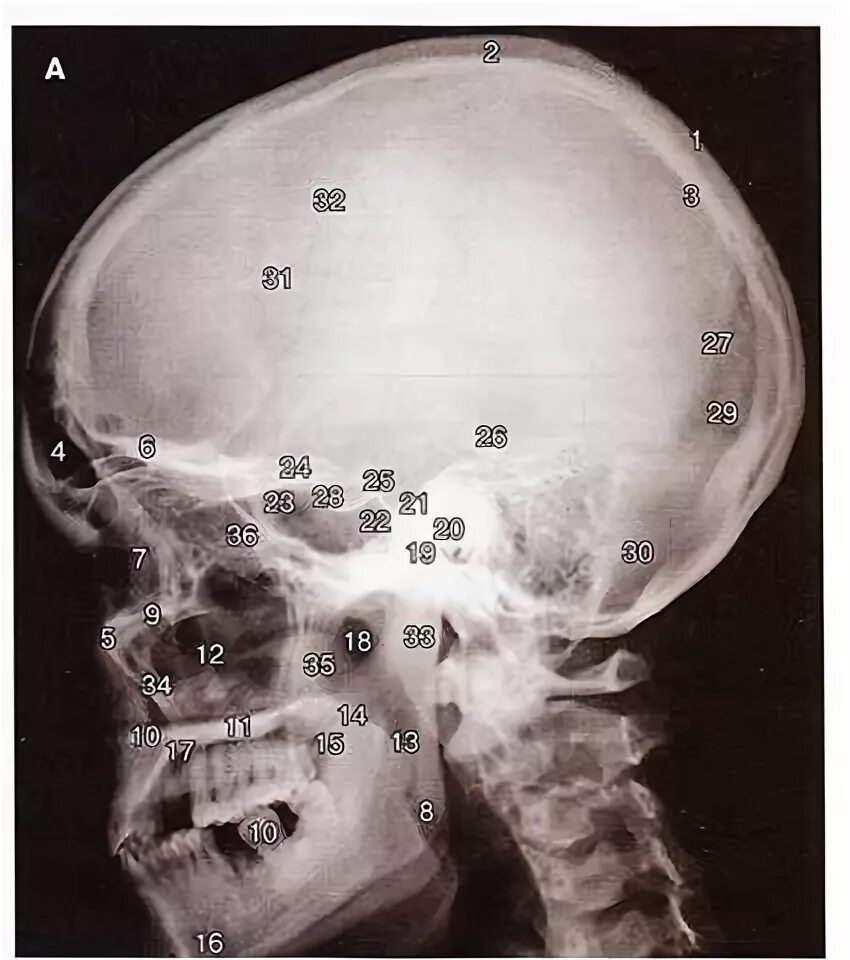

Проекции рентгенограмм черепа